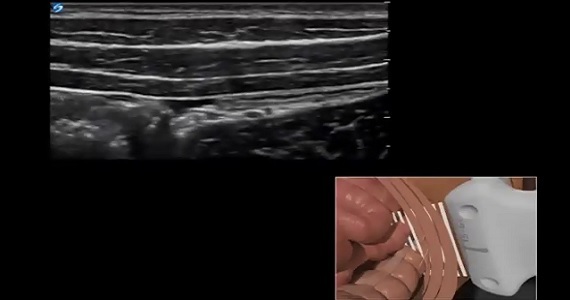

録音されたウェビナー 超音波誘導胸腺腫IおよびII ブロック 録音されたウェビナー 超音波誘導胸腺腫IおよびII ブロック 日付: 火曜日, 6 月 26, 2018 – 09:20 PDT バンディ・ガフニー II、MD、MS、地域麻酔科医、急性疼痛医学スペシャリストは、超音波誘導胸筋IおよびII ブロック1を発表しています。このウェビナーでガフニー博士は、胸筋IおよびIIブロックの適応症と臨床的使用法について説明し、胸部、側胸壁および腋窩の解剖学的および超音波解剖学的構造を説明し、胸骨穿孔の成功のための適切な針および局所麻酔の配置を示し、 IIブロック、および超音波誘導麻酔を行うための臨床真珠について論じています。